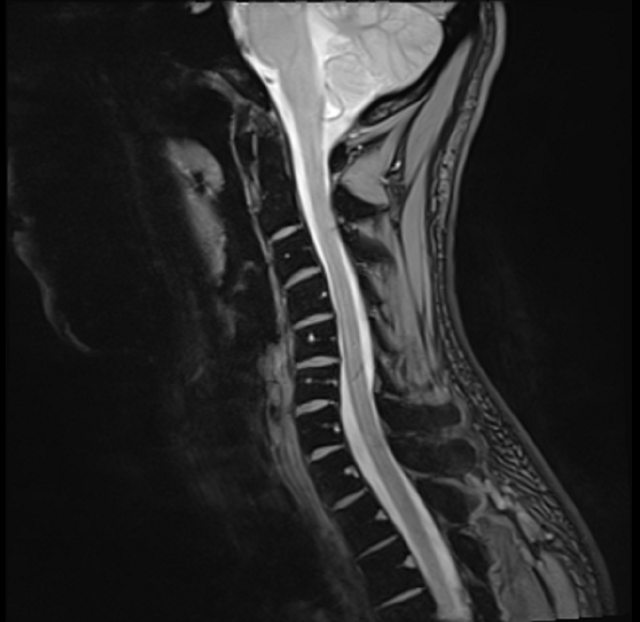

--- 目前做了檢查 - 頸椎 MRI 似乎不太正常 - Slight kyphosis of cervical spine (頸椎排列後凸) https://i.imgur.com/BUnDwSd.png

https://i.imgur.com/tC0JNs6.png